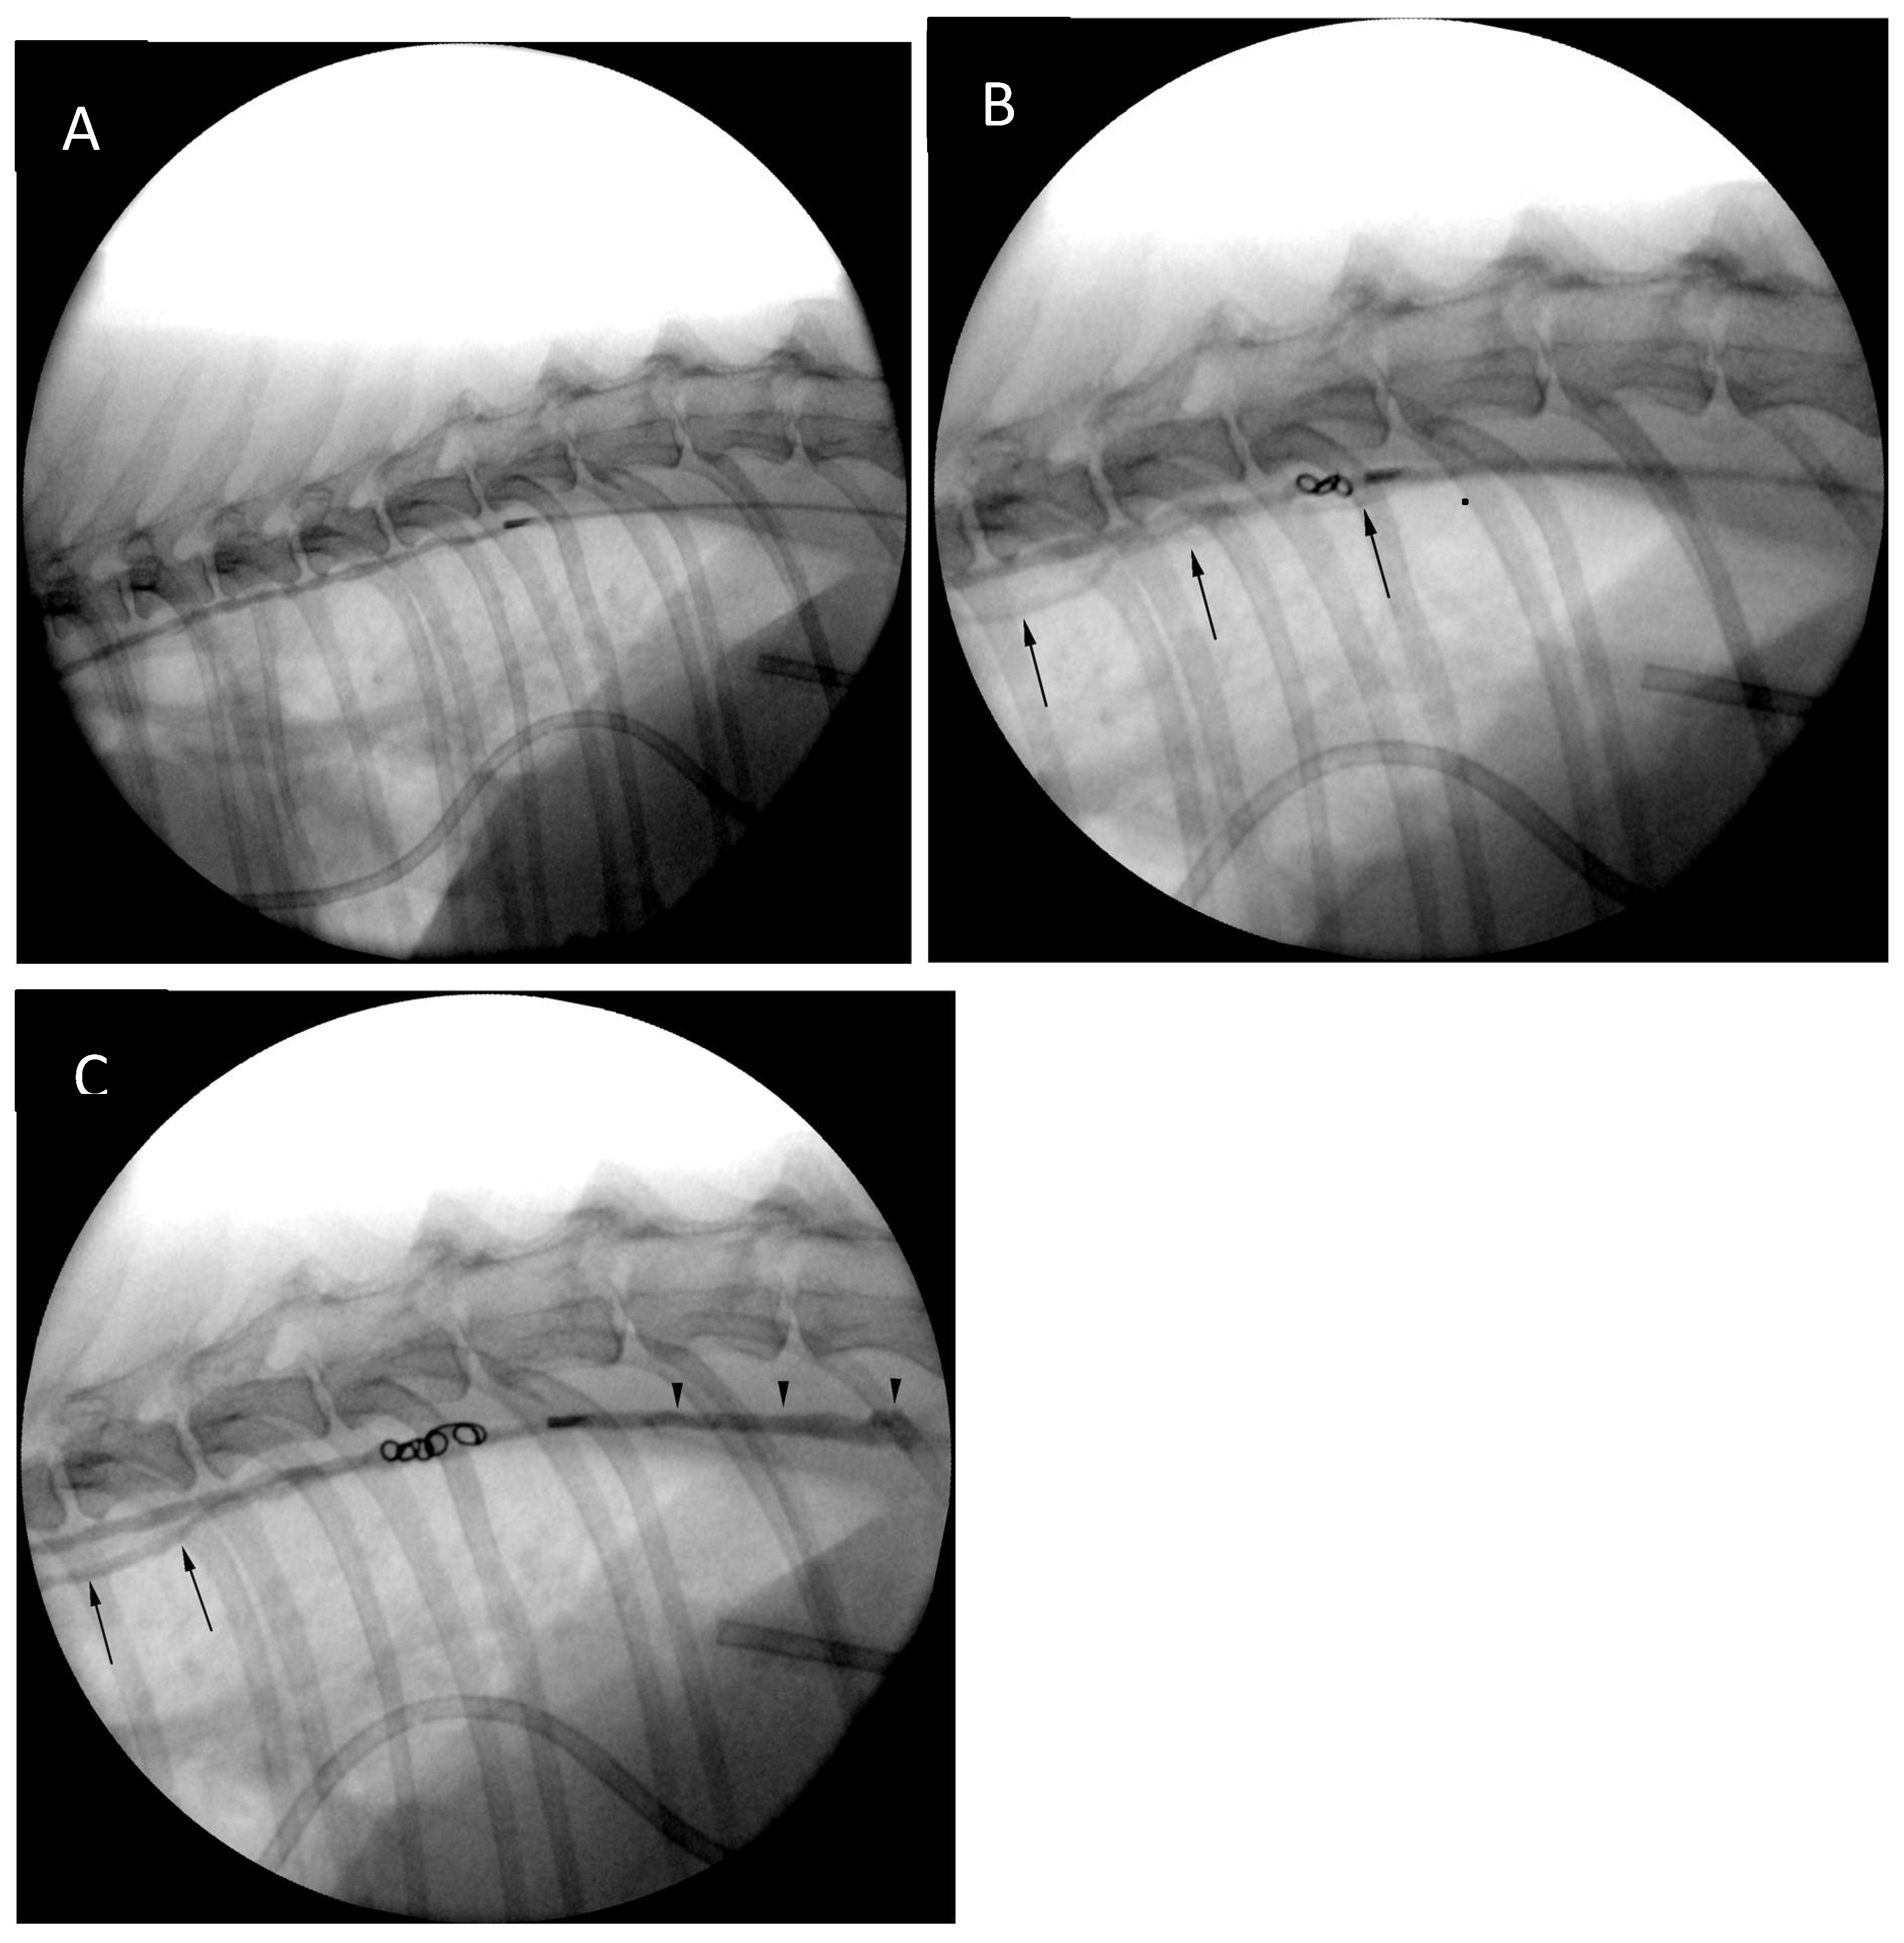

The ultrasound probe was removed from the patient’s skin and further stages of the procedure were performed with guidance of a portable fluoroscopy unit (Zenition 70, Philips). The guidewire was removed, and a lymphangiogram was performed with 50:50 iohexol:0.9% sodium chloride mixture revealing presence of lymphangiectasia and leakage of contrast medium at the level of the cranial mediastinum (Figure 6).

After the catheter had been retracted to the lever of the cranial endplate of the T11, the image was magnified, and another lymphangiogram performed. Two 0.018-inch 2 mm x 2 cm hydrogel coils (Azur CX and Azur HydroCoil, Terumo) were deployed in the caudal thoracic duct with control lymphangiograms after each deployment. Opacification of additional thoracic duct branches could be appreciated (Figure 7). The operator's intention was to deploy an additional 0.018-inch pushable, fibered coil, unfortunately, an 0.035-inch coil was inserted into the catheter instead by mistake. This resulted in the coil being stuck in the proximal portion of the catheter. As further injections, including the injection of neat contrast (Omnipaque 300, GE Healthcare) the procedure was continued without catheter exchange. The catheter was flushed with 5% dextrose in water and embolization of the thoracic duct and cranial portion of the cisterna chyli was performed with combination of n-butyl-2-cyanoacrylate glue (Histoacryl, B Braun) and ethiodized oil (Lipiodol Ultra Fluid 480 mg I/ml, Guerbet) in 1:2 (glue-to-oil) ratio. The embolic mixture was injected under continuous fluoroscopic monitoring while retracting the microcatheter (a ‘pull-back’ technique) to obtain adequate filling of the TD and CC (Figure 7). No evidence of glue embolization into the venous circulation could be appreciated. Subsequently, the access needle was removed, and sterile dressing (Sorbact, Abigo Medical AB) applied. No skin sutures were needed. No dorsoventral imaging was performed at the time of the TDE due to limitations in room setup, although, it might have provided additional anatomical information [15].

Figure 6. Early (A) mid (B) and late (C) fluoroscopy frames from the initial lymphangiographic study. The microcatheter tip positioned at the level of the T6-T7 intervertebral disc space can be seen (black arrowheads). Dilated and tortuous cranial mediastinal lymphatics ca be appreciated on panel (B) and (C) with impression of contrast extravasation into the mediastinum (panel C, black arrows).

Figure 7. (A) Lymphangiogram after repositioning of the microcatheter to the level of the cranial endplate of T11. Additional lymphangiograms after placement of the first (B) and second (C) microcoil. Opacification of additional lymphatic channels (black arrows) can be seen after coil deployment. Reflux of contrast along the microcatheter can be seen after deployment of the second coil (panel C, black arrowheads), likely due to increasing resistance to contrast medium injection.